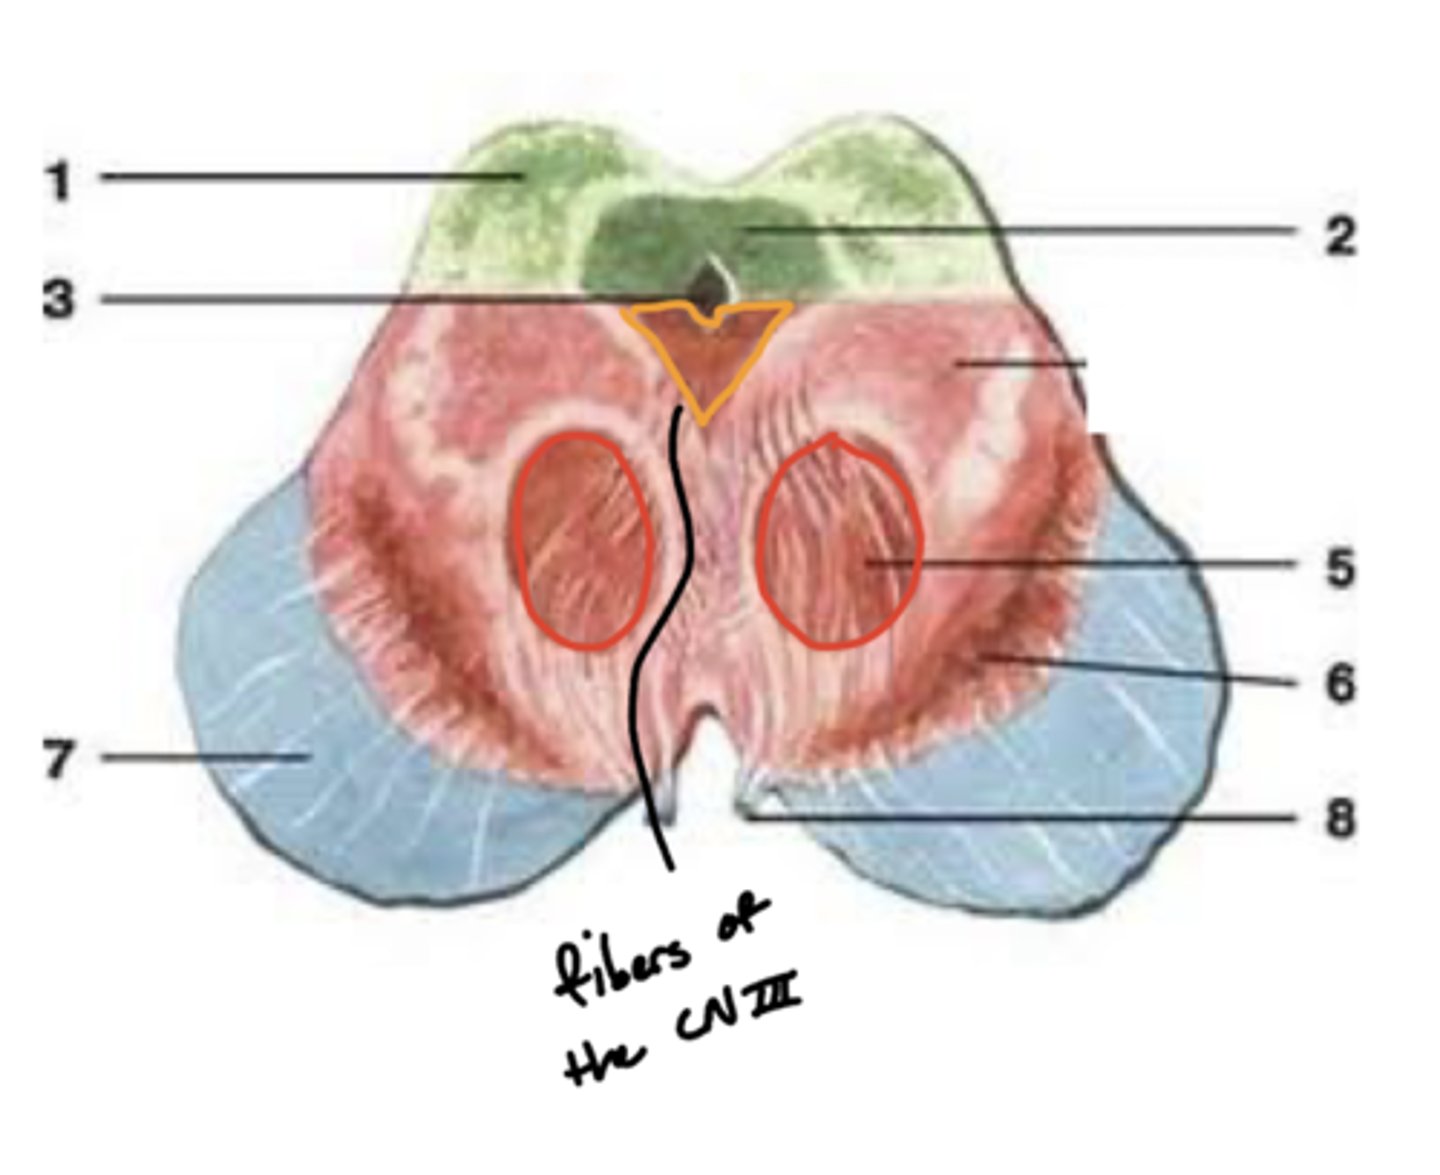

What are the red nuclei?

projection fibers from the (contralateral) cerebral hemisphere down the spinal cord to limbs

image -- 5

What other notable structure should you see if you see two red nuclei?

"if you see two red nuclei you're at the superior colliculus level"

Where does CN III exit the brainstem?

interpeduncular fossa (ventral surface)

Where are the CN III and IV nuclei?

tegmentum mesencephalon

CN III -- anterosuperior

CN IV -- posteroinferior

What is the floor of the 4th ventricle?

tegmentum pons

image -- green

What cranial nerve nuclei are in the tegmentum pons?

1. CN V (5)

2. CN VI (6)

3. CN VII (7)

4. CN VIII (8)

What is the superior medullary velum?

membrane that forms the superior portion of the 4th ventricle roof

image -- 7

What is the inferior medullary velum?

membrane that forms the inferior portion of the 4th ventricle roof

image -- 1